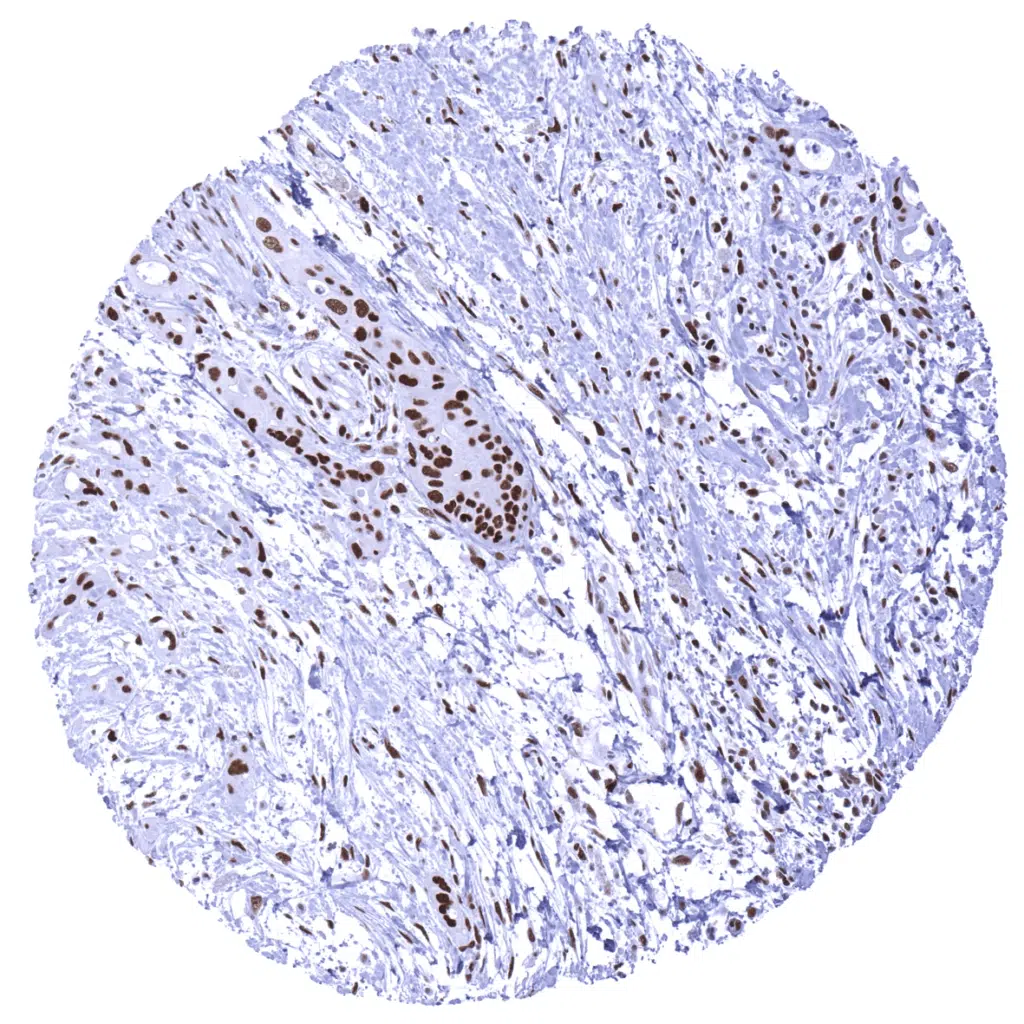

MSH2 antibody [MSVA-902M] HistoMAX

Colon – Colorectal adenocarcinoma showing a markedly reduced MSH2 immunostaining in cancer cells as compared to stromal and inflammatory cells